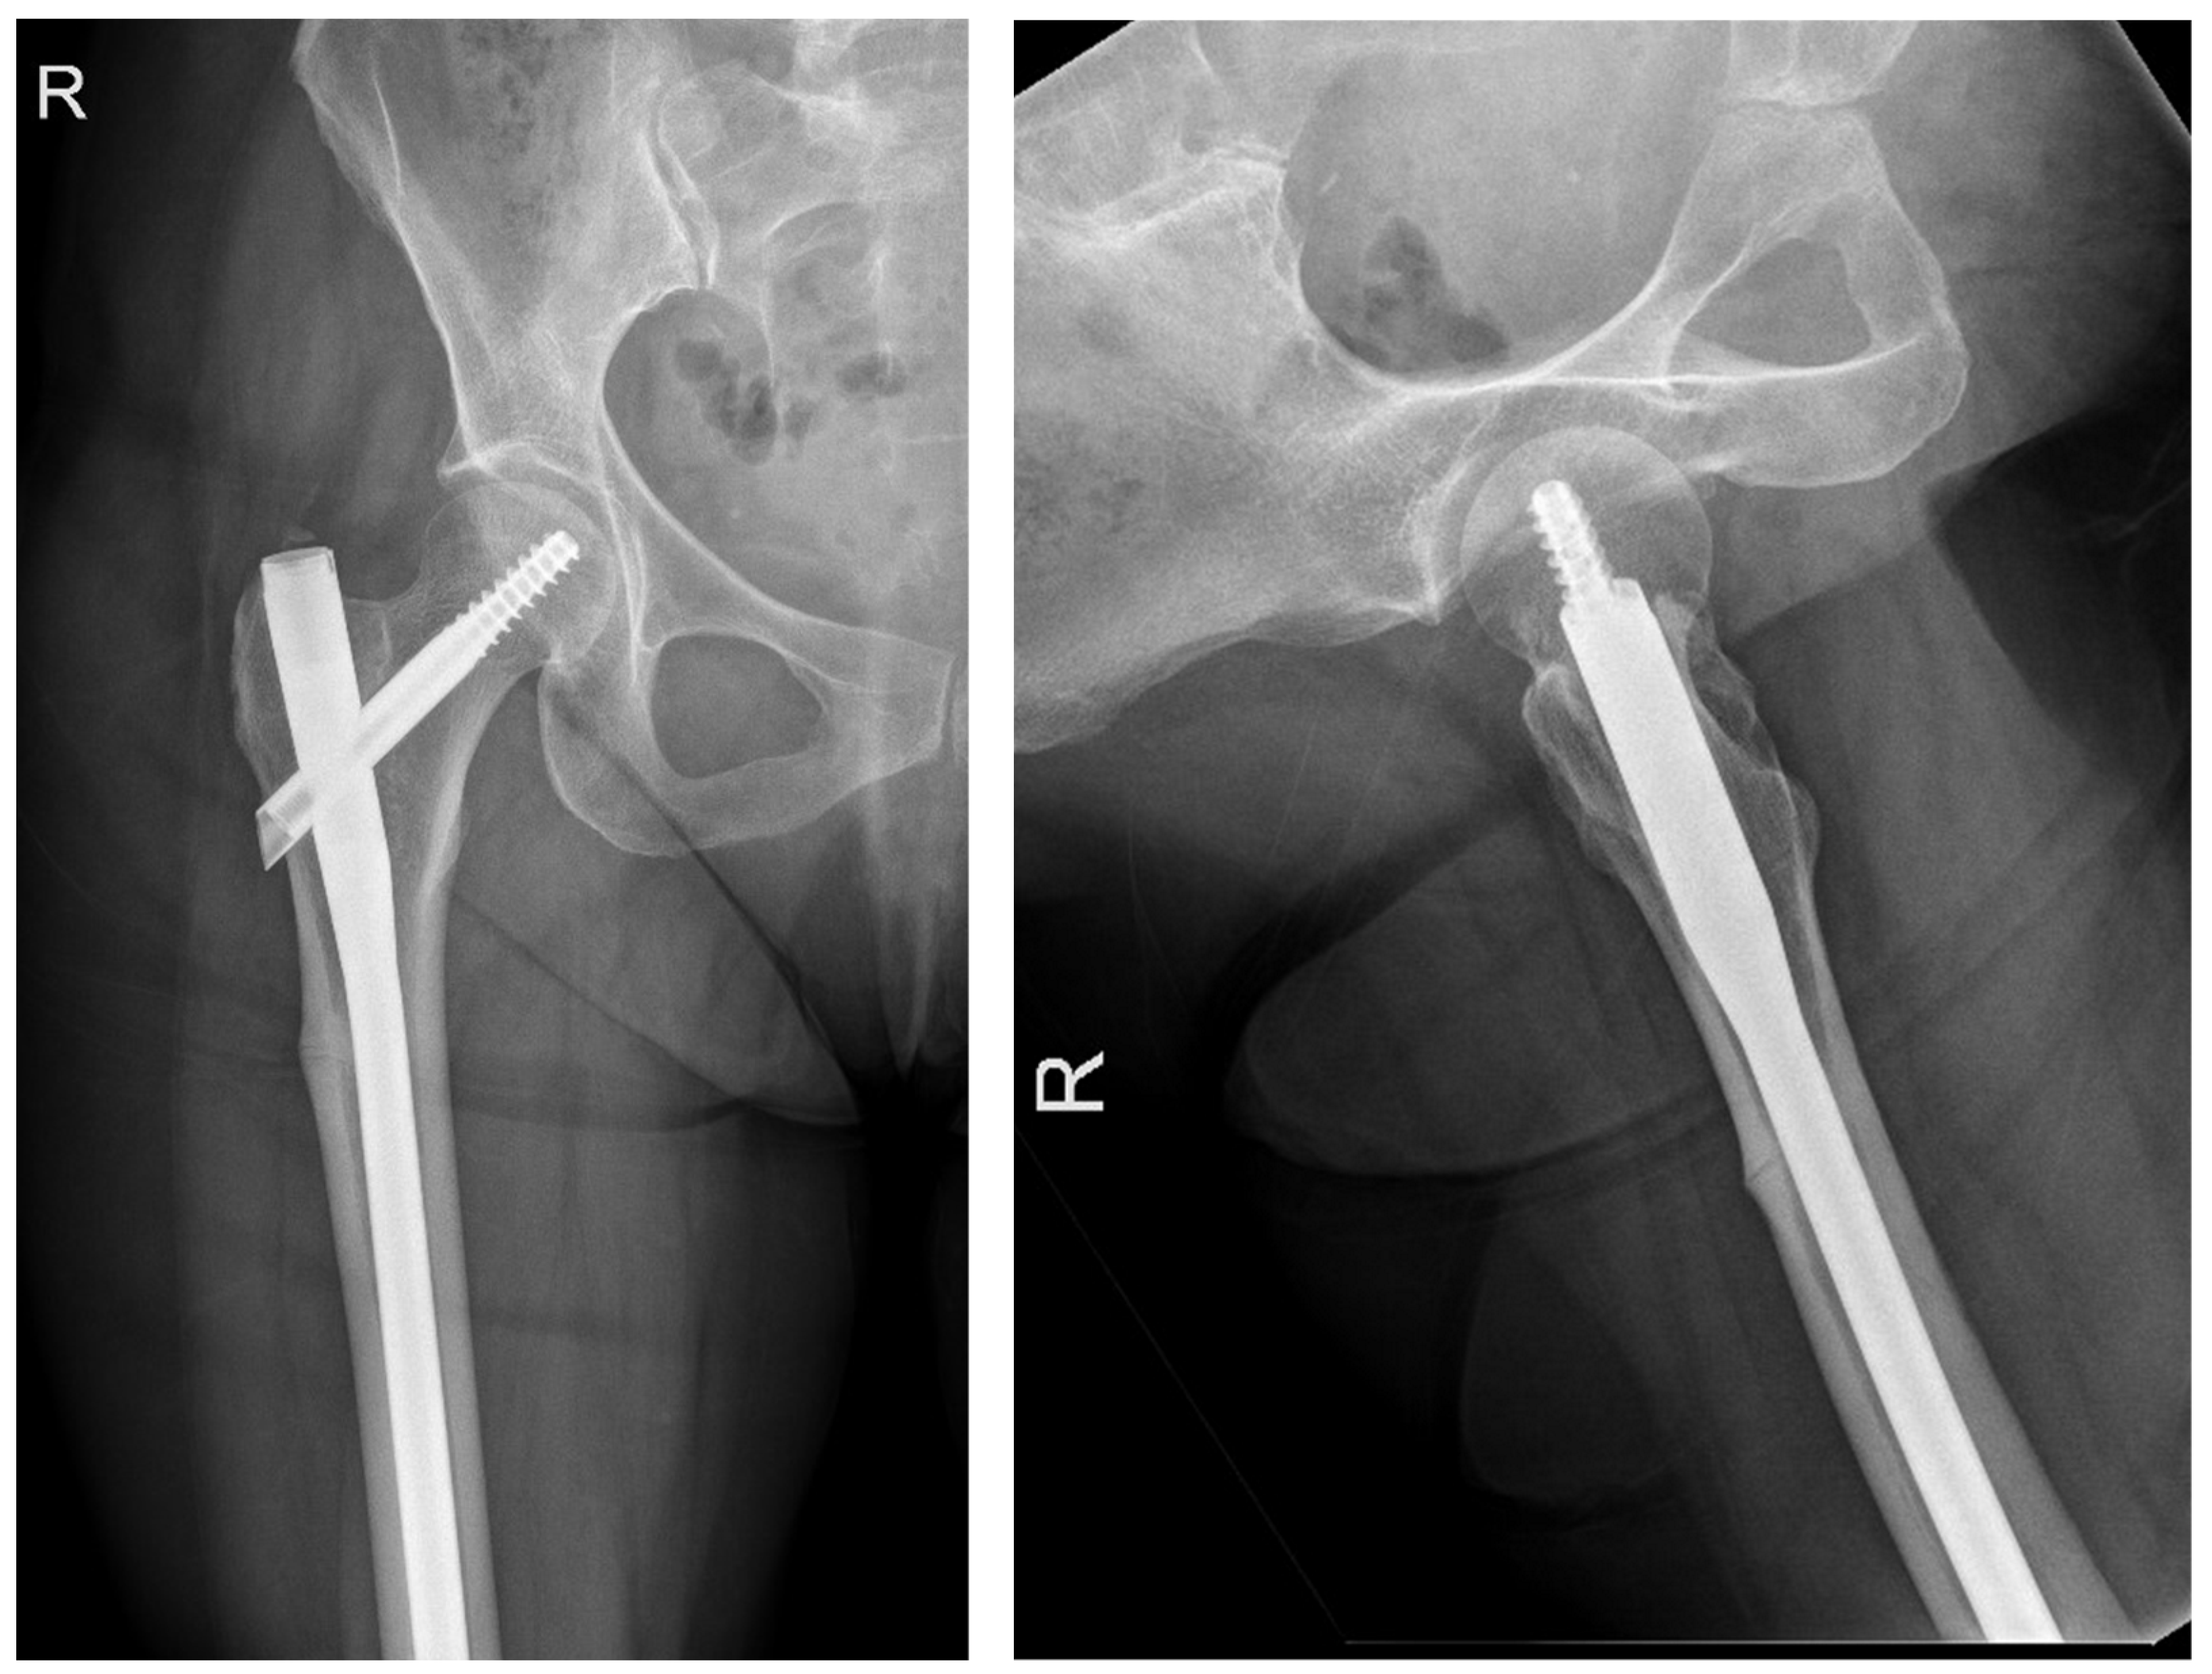

The following radiographs present the initial radiographs from the day of injury along with those obtained during the final OPD follow-up of the patient. The sequence presents radiographs demonstrating full radiological union (Scheme 1 and Scheme 2) and X-rays with no evidence of fracture healing at the final OPD follow-up (Scheme 3 and Scheme 4).

Scheme 3. X-ray of right femur AP view (left) and lateral view (right) of atypical subtrochanteric stress fracture—July 2022.

Jcm 14 02858 sch003